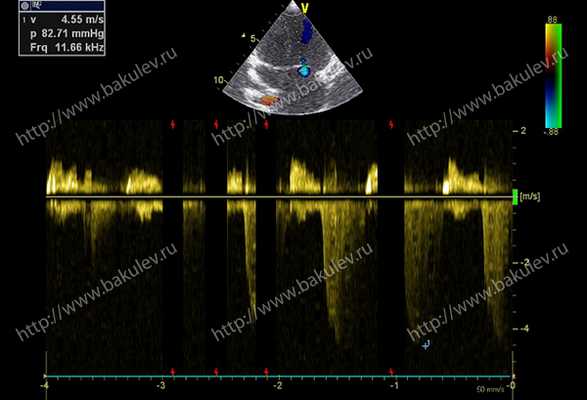

Эхокардиография (ЭхоКГ): Сердце расположено справа. Расширены камеры сердца, больше правые. Гипертрофия миокарда обоих желудочков, перегрузка объёмом правых камер. Аорта и лёгочная артерия смещены в правый желудочек. Верхушка сердца выполнена правым желудочком. Расширен коронарный синус в левом предсердии. ДМЖП подаортальный 17 мм, вторичный ДМПП 12-14мм. Снижена сократительная способность левого желудочка, ФВ — 53%. Расширение аорты в области синусов, кровоток ускорен. Выражена недостаточность трикуспидального клапана. Высокая лёгочная гипертензия, среднее давление в лёгочной артерии — 102,7 мм. рт. ст.

Рис 4,5 — Результаты ЭхоКГ-исследования